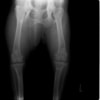

術前正面像

術後左後肢正面像

術前のTPAは左後肢33.1°右後肢26.8°でしたがTPLO実施により左後肢5.5°右後肢12°に矯正されました。